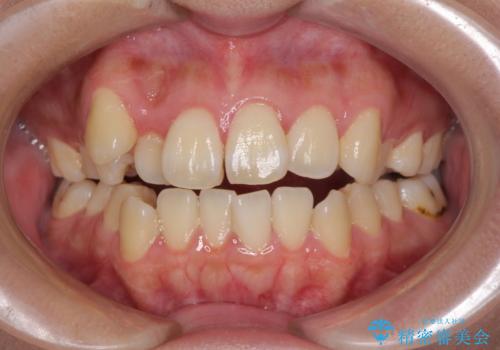

- 八重歯と叢生を気にして来院された患者様です。

上下の前歯が非接触であり、叢生や八重歯が顕著であったため、上顎左右第一小臼歯2本を抜歯して排列することとしました。

抜歯により移動量が多くなるため、ワイヤーや補助装置を活用し、その後インビザラインによる矯正治療を行うこととしました。